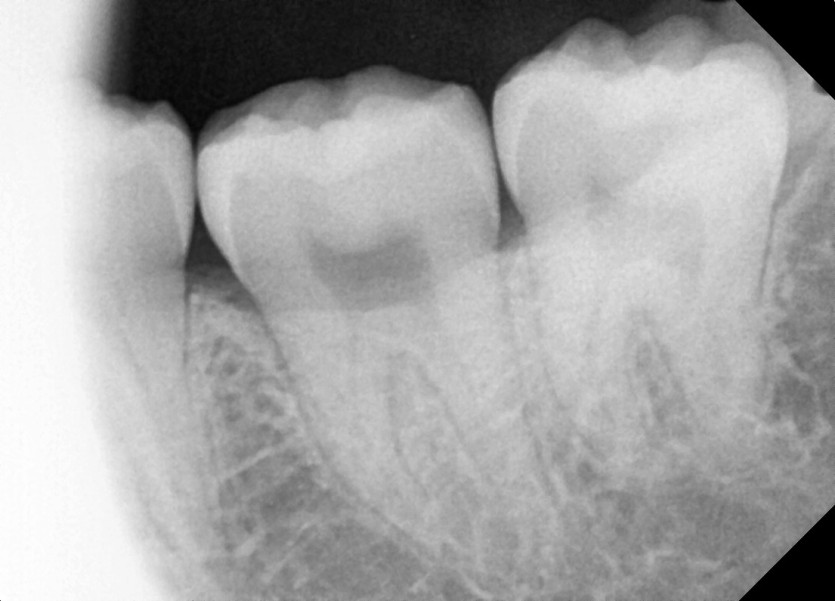

#38 사랑니 발치

구강 외과 전문의가 당일 발치했습니다.